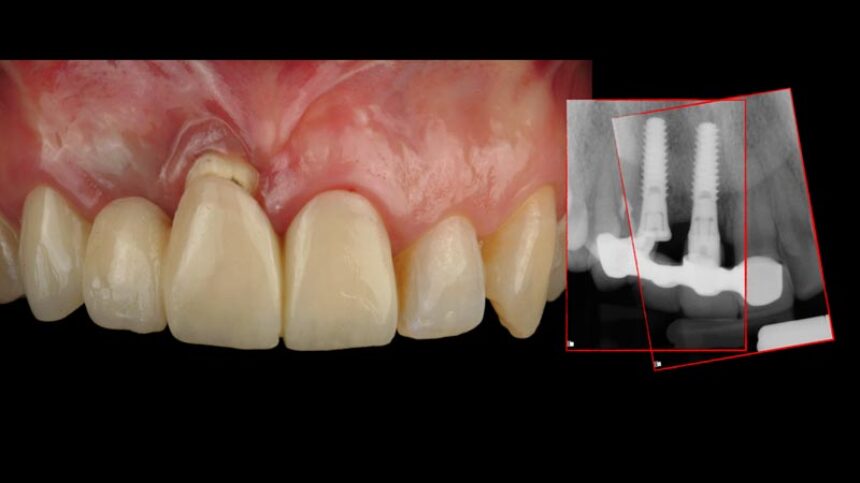

The goal to create a harmonious “esthetic” outcome around dental implants that mimics the surrounding dentition and soft-tissue condition as well as morphology is indeed difficult to create and maintain long term.

In this presentation a comprehensive approach to optimize functional and esthetic results with immediate implant placement will be discussed by blending surgical, technical, and restorative steps into one successful protocol will be presented thoroughly.

Immediate surgical and restorative protocols facilitate superior esthetic and functional success. However, strict guidelines for atraumatic intervention, implant primary stability, bone packing, connective tissue graft and preservation of existing anatomic structures must be carefully followed. Digital planning plays a fundamental role to achieve such a desired results.

On the other hand, the subepithelial connective tissue graft (CTG) is a favored option to treat and prevent gingival and peri-implant soft-tissue recessions. It is usually placed in combination with a coronally advanced flap or with an envelope flap or pouch. This lecture will focus on the difference on protocols when it comes to surgical and prosthetic criteria to treat anterior implants using as a volume maintainer only soft tissue grafting procedures. Techniques and tools will be discussed in order to reach such results around anterior implant treatments.